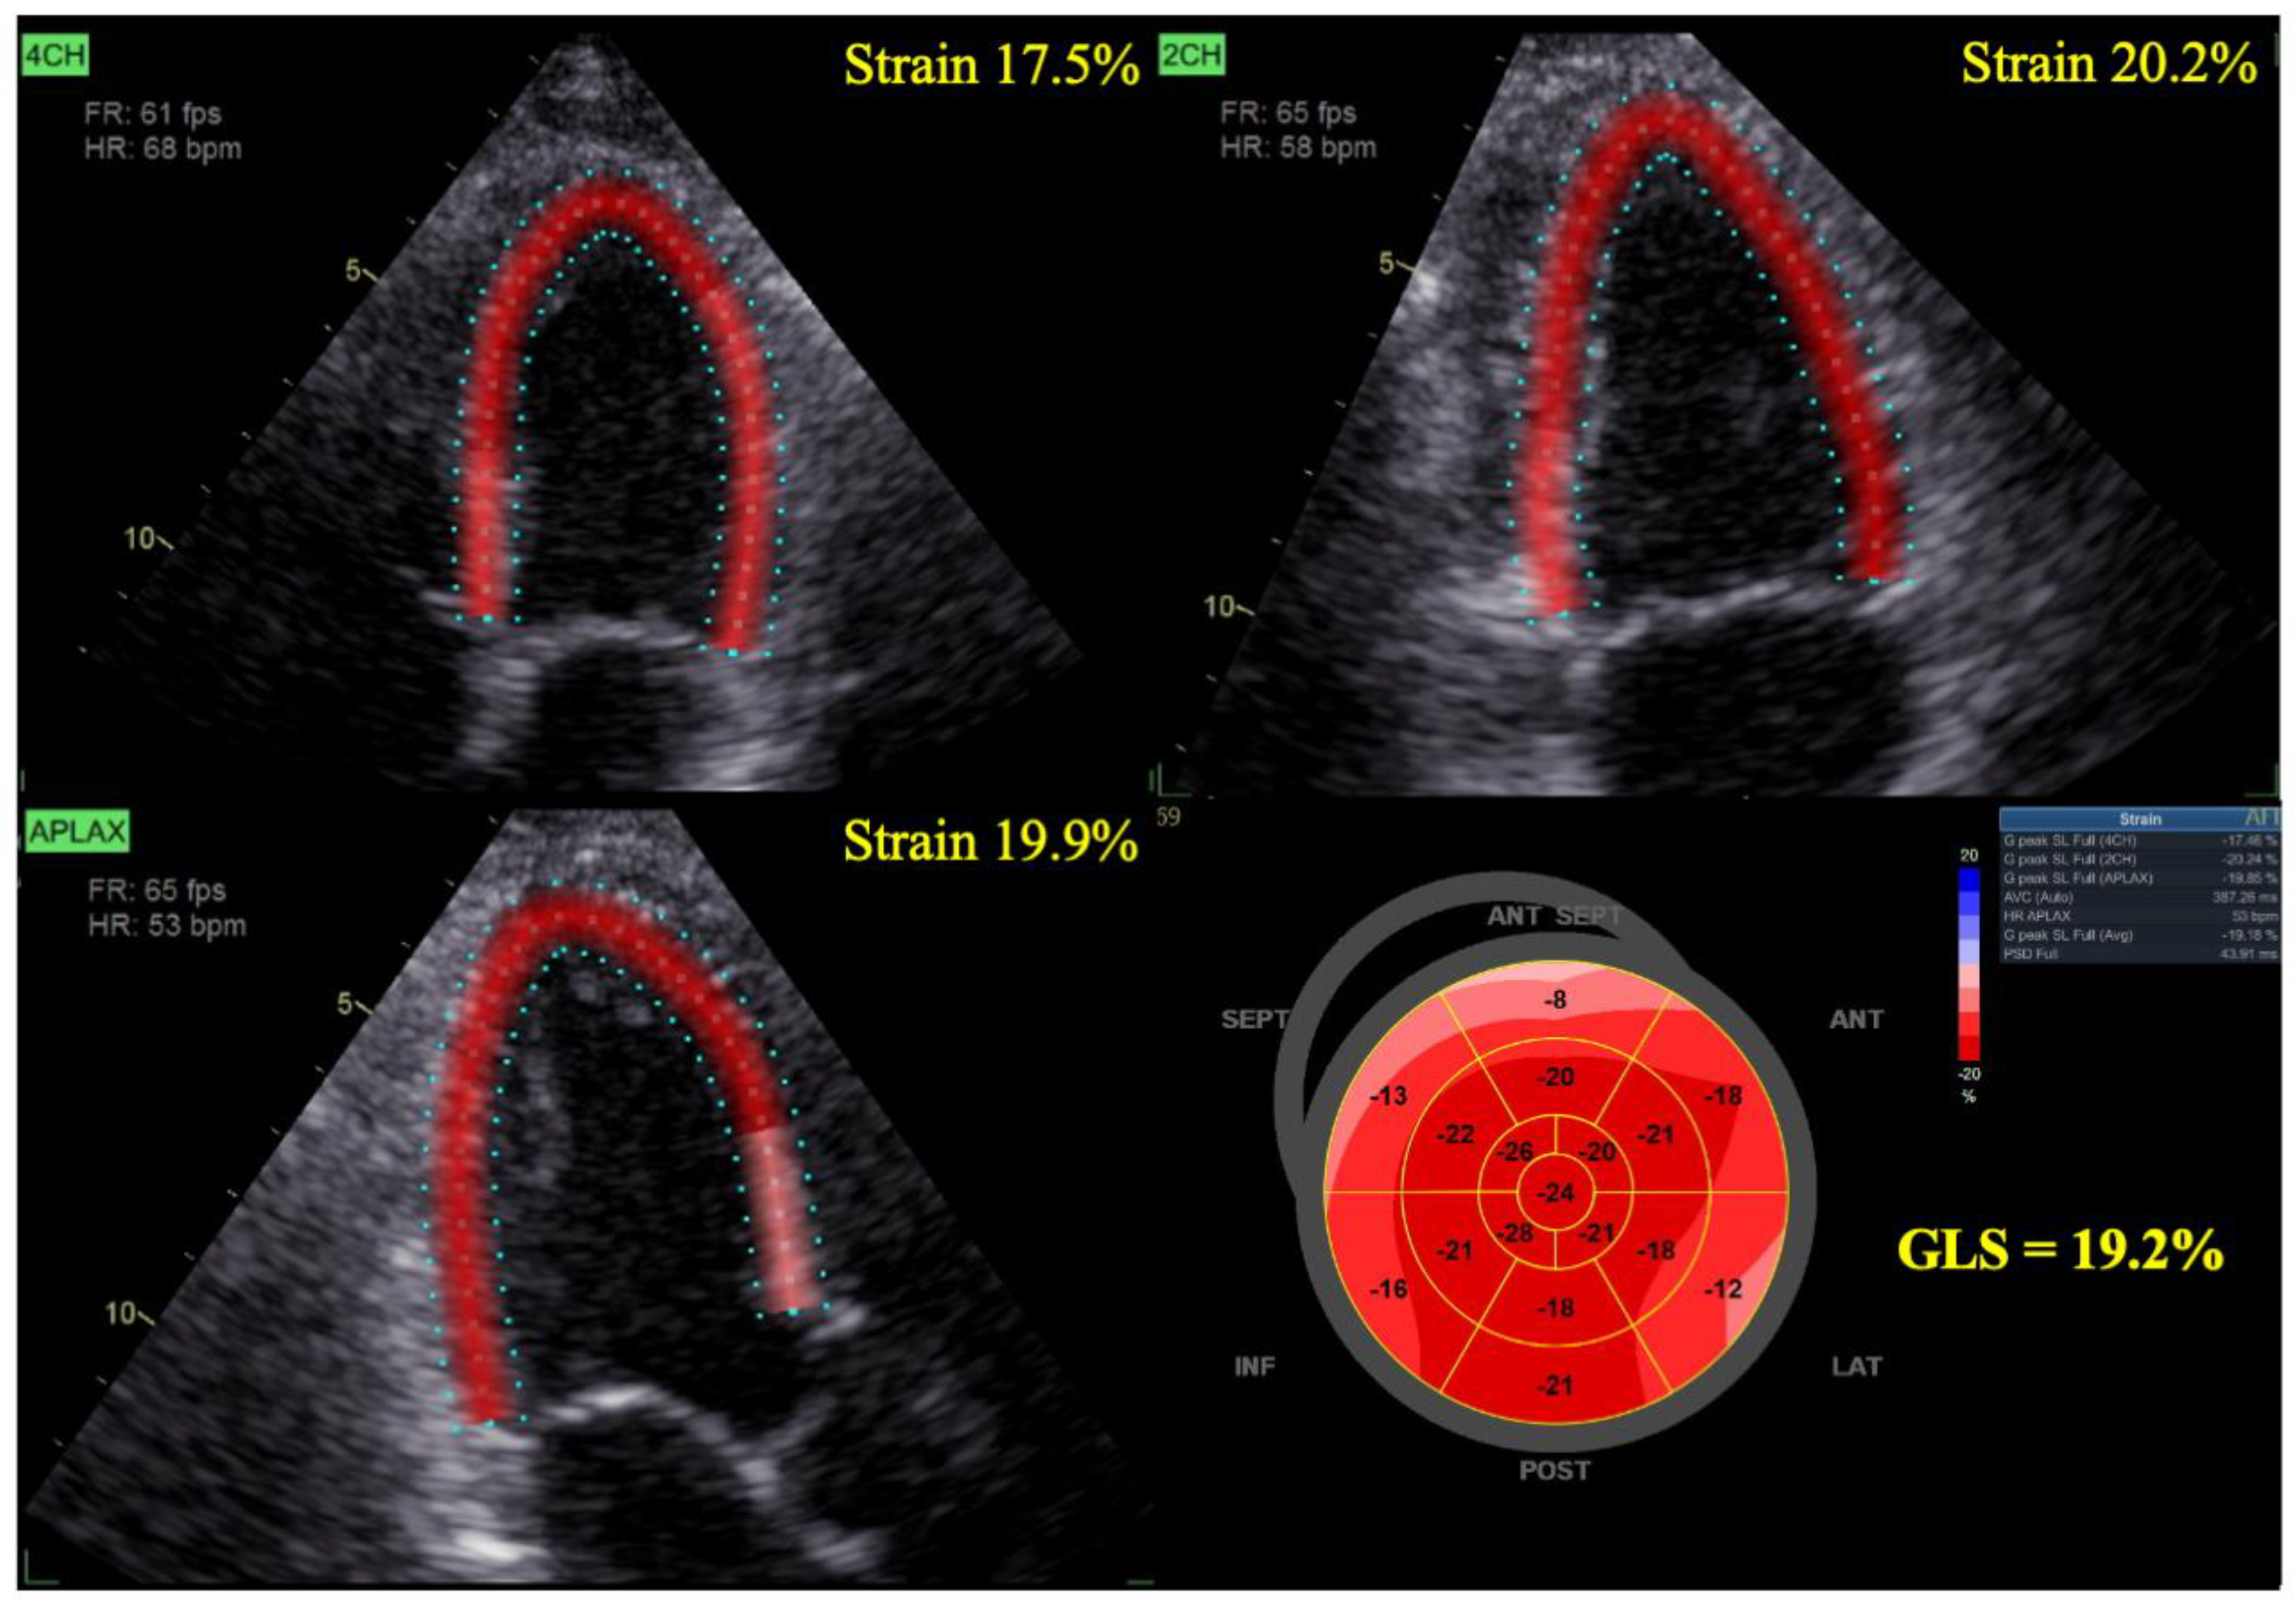

2. CTRCD

3. LS